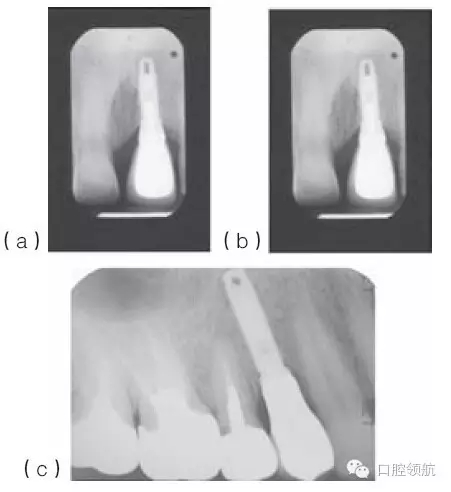

種植體適當?shù)那蓄i/ 頸向位置,有利于建立逐漸過渡的外形和正常的穿齦形態(tài)。種植體切頸/牙合頸向的定位,很大程度上取決于現(xiàn)存骨的位置(圖10.33a~c),以及滿足美學需求的頸部過渡形態(tài)。因為種植體的平臺接口為小直徑的圓形,而齦緣的修復體截面為直徑較大的不規(guī)則幾何形態(tài),中間需要一定的過渡才能滿足美學的需求。一般來說,種植體植入到鄰牙釉牙骨質界稍下方,以使所需的形態(tài)學改變逐步發(fā)生(圖10.34)。

圖10.33 (a)金屬烤瓷冠粘結后的根尖片。(b)種植體位于鄰牙釉牙骨質界根方3mm的根尖片。切嵴到種植體頂部的距離太大,導致種植體金屬部件可能承受較大的力。(c)種植體植入到嚴重骨吸收的上頜第一前磨牙區(qū)。種植體到面的距離幾乎等于種植體的長度。

圖10.35 (a)上頜中切牙周圍的牙齦乳頭充填,形成了良好的軟組織外觀。(b)(a)圖中種植體冠的X線片顯示,相對修復體和種植體來說,鄰面牙槽骨處于理想的位置。(c)下頜種植支持式的局部固定義齒,采用牙齦色的烤瓷來改善頸部外觀。(d)復制的上頜全口義齒的前面觀,一側的頰側翼板被去除,以模擬上頜全口固定義齒的外觀。(e)右側觀唇部的支撐效果。(f)左側觀唇部的支撐效果。這一側對唇部的支撐明顯不如對側。